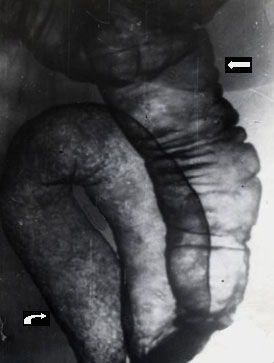

Неспецифический язвенный колит.

Рис. 1. Поражение всей сигмовидной кишки (фигурная стрелка): кишка несколько расширена, стенки её ригидные, гаустрация отсутствует, пневморельеф имеет характерный для неспецифического язвенного колита равномерно зернистый вид. Восходящая кишка интактна (прямая стрелка).